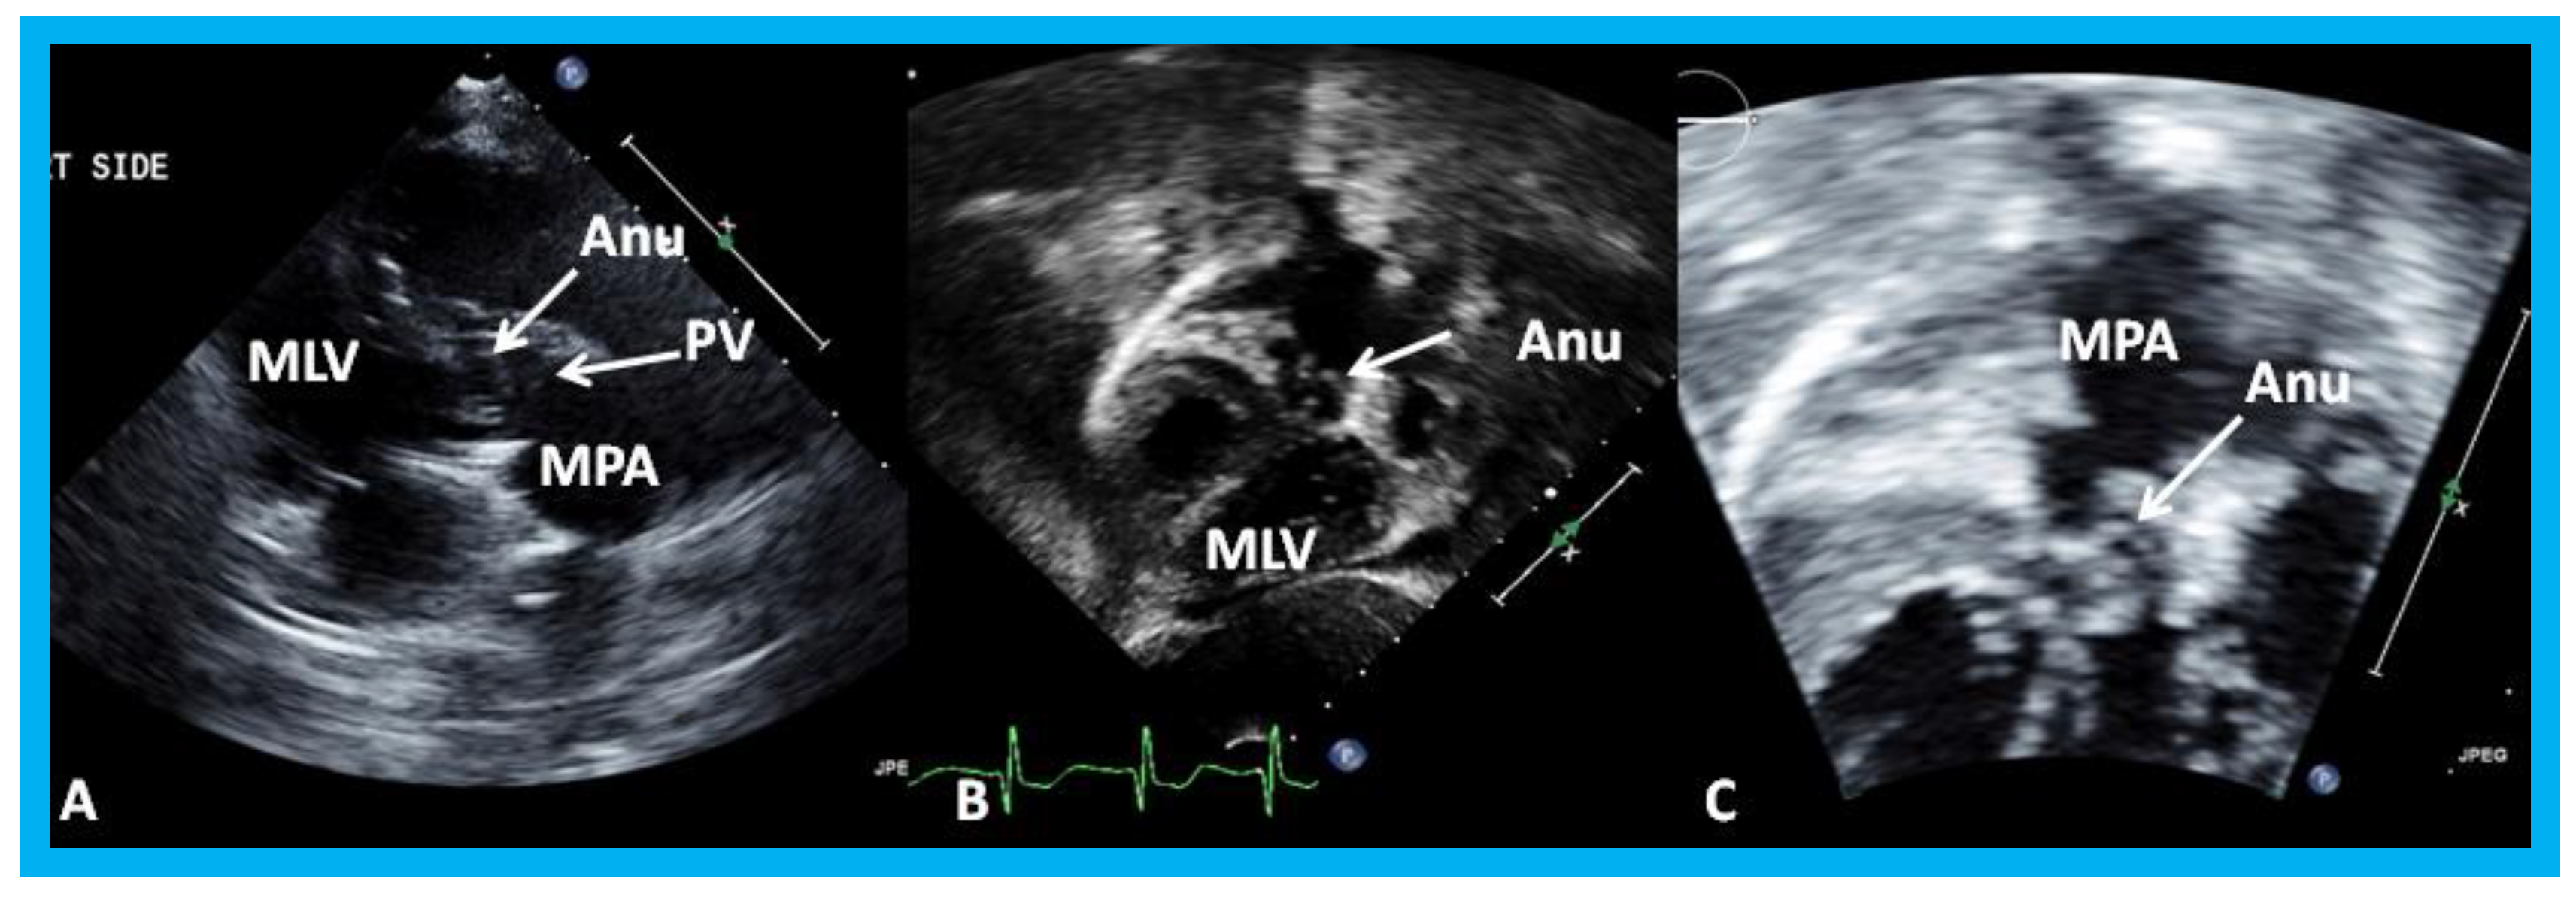

Figure 19. Selected video frames from a right parasternal (A) and subcostal four chamber (B) views of the morphologic left ventricle (MLV) demonstrating aneurysm (Anu) projecting into the MLV outflow tract, producing obstruction: The Anu is located just below the pulmonary valve (PV). The main pulmonary artery (MPA) is dilated. (C) An enlarged view of B illustrating the aneurysm and MPA dilatation. Reproduced from Yarrabolu T.R., et al. [23].